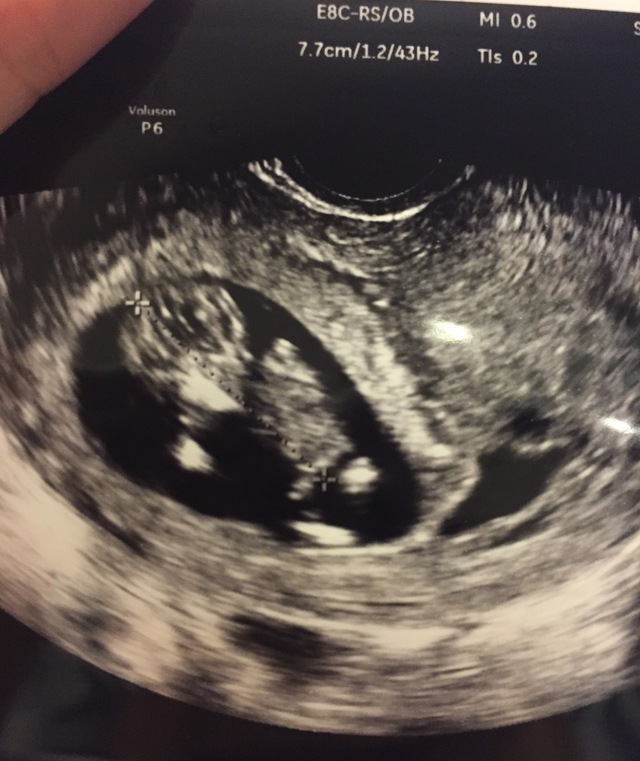

11週0日(11w0d・性別不明)|kiki34 さん(28歳)

エコー写真撮影時のエピソード:

両親や姉妹に報告するときにエコーの写真を見せました。とても喜んでもらえました。 毎回のエコー写真はアルバムにしてコメントをつけて保存するようにしています。

だんだん大きくなっているのが目に見えてわかりコメントを書くことによってその時の気持ちがわかるようになるので見返してて楽しいです。将来は産まれてきた我が子にあげる予定です!